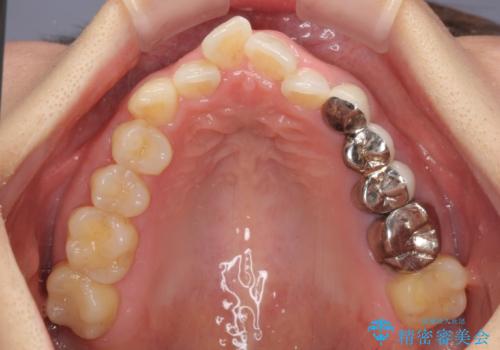

- 上下前歯のデコボコと銀歯のブリッジを気にして来院された患者様です。

装着されているブリッジを切断して矯正治療を行うことや、手間をかけずに早めに治療を終えたいとのことで、目立たないワイヤー装置による矯正治療を行うこととしました。

矯正治療後には切断したブリッジをオールセラミックブリッジに置き換えることとしました。